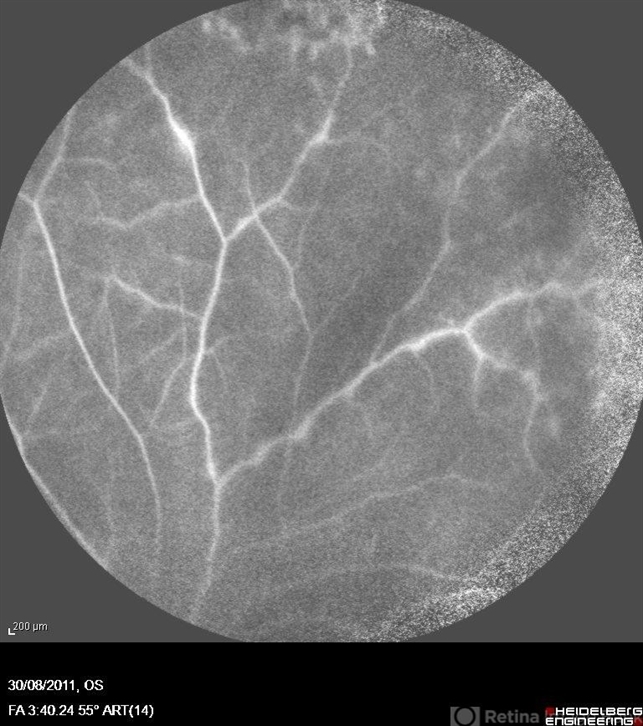

- occlusive vasculitis

- Azucena Rios Macula Retina Consultores Mexico

Fundus camera

heidelberg Spectralis - Description

- A 36-year-old women with panuveitis and bilateral occlusive vasculitis.